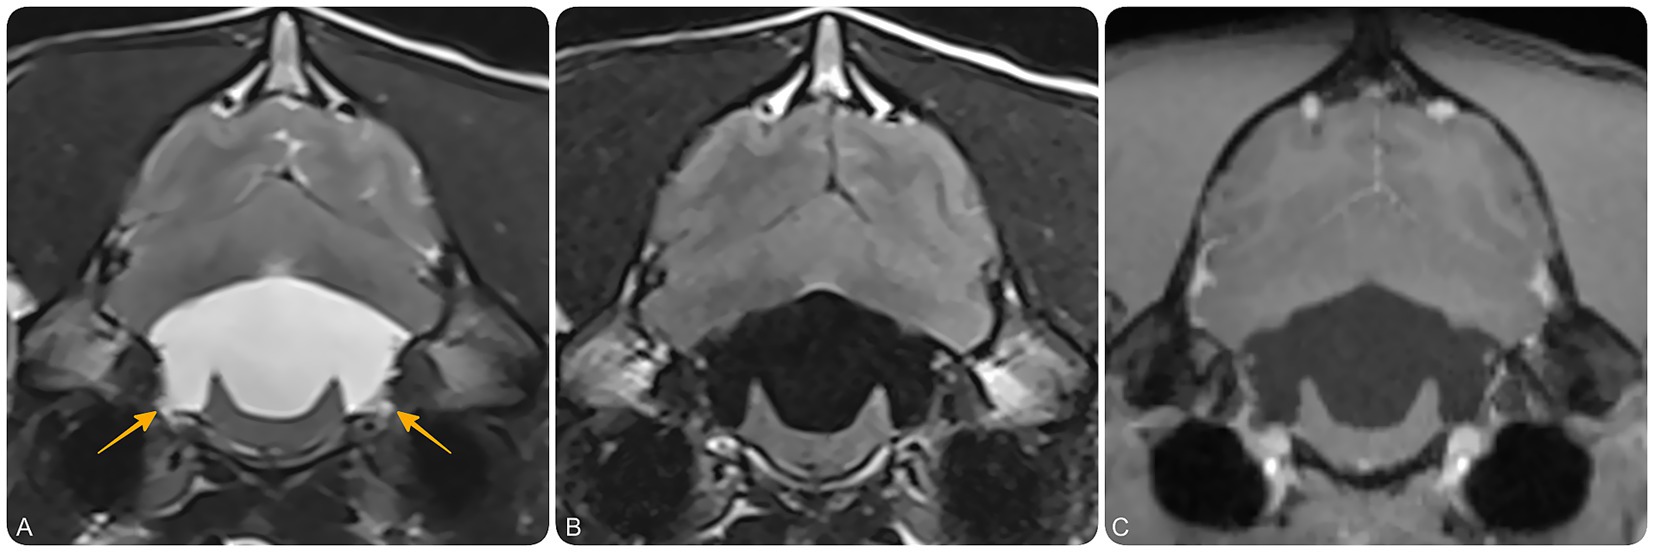

Figure 2. Magnetic resonance imaging (MRI) of the brain at the level of the fourth ventricle and lateral recesses. Transverse T2-weighted (A), T2-FLAIR (B), and T1-weighted post-contrast (C) MR images at the level of the lateral apertures of the fourth ventricle. These images demonstrate bilateral dilation of the lateral recesses (yellow arrows), suggestive of impaired CSF outflow at the level of the lateral apertures. No contrast-enhancing or intraventricular cystic lesions are identified.

MRI findings (Figures 1A,B) revealed severe, diffuse dilation of the entire ventricular system, including the lateral ventricles and olfactory recesses, third ventricle, mesencephalic aqueduct, fourth ventricle, and lateral recesses (Figure 2). Additional findings included flattening of the interthalamic adhesion, compression of the cerebellum and brainstem, and supracollicular fluid accumulation with concurrent expansion of both the third ventricle and the quadrigeminal cistern. Within the ventricular system and the syrinx, hyperintensity on FLAIR and mild signal voids on T2w images were consistent with rapid and turbulent CSF flow. A thin band isointense to gray matter on both T1w and T2w images was observed along the dorsal and lateral aspects of the caudal portion of the fourth ventricle. Moderate periventricular hyperintensities on T2w and FLAIR images were consistent with hydrostatic interstitial edema. Effacement of the cerebral sulci was noted, along with dorsal displacement of the corpus callosum and partial absence of the septum pellucidum. At the level of the cervical spine, moderate scoliosis and severe syringomyelia were identified, accompanied by extensive spinal cord edema extending throughout the cervicothoracic region. No abnormal parenchymal or meningeal enhancement was observed following contrast administration. The ventricle-to-brain (VB) index, assessed on dorsal T2w images, was 0.69 (reference interval < 0.6) (14).

MRI findings revealed progressive loss of parenchymal volume, with an increase in VB index to 0.82 (RI < 0.6). A thin membrane within the fourth ventricle, better visualized on 3D-CISS, corresponded to the rostral medullary velum—a normal anatomical structure that becomes more conspicuous with ventricular dilation and altered anatomy, rather than a pathological septation or diverticulum. PC-MRI, together with conventional sequences and anatomical landmarks, demonstrated preserved intraventricular CSF flow but no signal to suggest outward flow from the region of the lateral apertures, supporting this location as the site of obstruction. These findings excluded a fourth ventricle arachnoid diverticulum and supported a diagnosis of obstructive hydrocephalus, most likely secondary to lateral aperture occlusion.